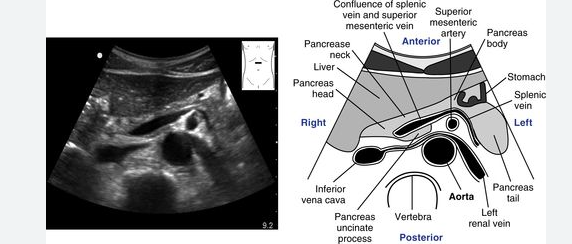

write down the anatomy.